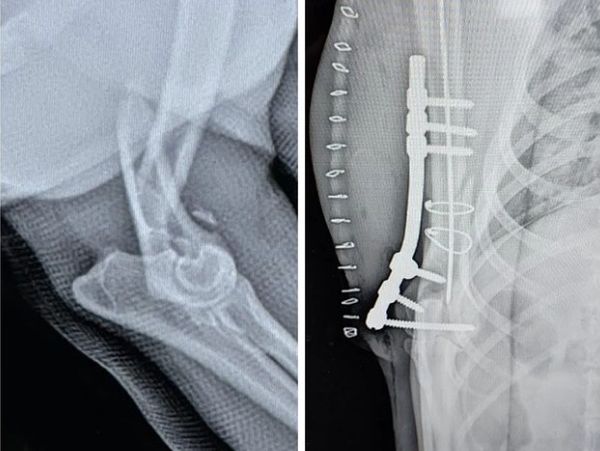

We perform many surgical procedures including spay, neuter, hernia repairs, and more advanced procedures asl weel. We perform advanced soft tissue and orthopedic surgery with veterinary surgery specialists. We perform more advanced surgeries such as Anterior Cruciate Ligament repairs, advanced cancer procedures, and upper airway syndrome surgery. We utilize the most advanced and up to date procedures such as platelet rich plasma infusions to facilitate healing and growth. Your general veterinarian and specialist work together to create the best and most appropriate treatment plan for your pet.

We provide a wide range of expertise surgical procedures such as exploratory laparotomy, liver lobectomy, splenectomy, laser treatment, orthopedic surgical treatments like fracture repair, cranial cruciate ligament disease repair, ACL repair, and more. Additionally, our expert doctors have extensive training in advanced orthopedic treatments and cutting-edge surgical techniques.